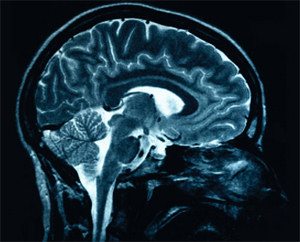

Patients in a vegetative state have intervals of wakefulness, but seem to be unaware of themselves or their surroundings, a Lancet study has found. The researchers did an electroencephalograph (EEG) on patients with both traumatic and non-traumatic brain injury in a vegetative state. The researchers used a test that involved motor imagery, encouraging the patients to imagine moving their right-hand fingers and toes. Such tests are universally considered a reliable indicator of awareness.

The researchers found that 3 (19%) of the 16 patients tested who were diagnosed as being in a vegetative state could reliably and repeatedly respond to EEG commands, despite the fact that they were behaviourally unresponsive. The study found that many vegetative patients are misdiagnosed. The researchers wrote that a new EEG method that is “cheap, portable, widely available, and objective” could be used to rediagnose patients who, seem “vegetative” in their behaviour but who might still have some awareness and cognitive function. ~ Lancet, Nov 10